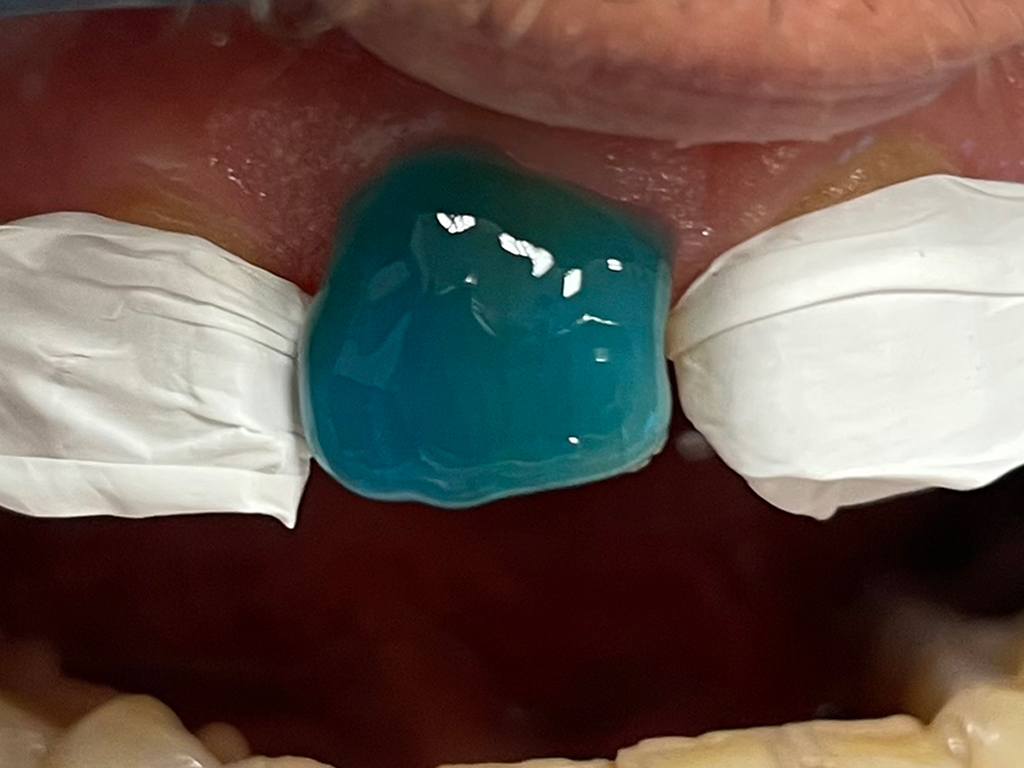

Per Isolare i denti adiacenti in corso di cementazione di corone, faccette, intarsi

Ideale per proteggere gli elementi dentali adiacenti alle cementazioni di ponti, intarsi, faccette. A differenza dei fogli di diga o delle matrici trasparenti in policarbonato non crea spessore, evita l’adesione dei cementi, facilita la rimozione degli eccessi